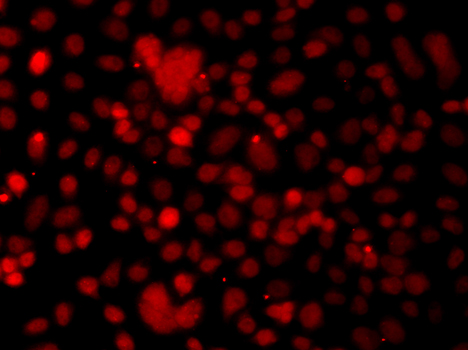

Immunofluorescence analysis of A549 cell using SNAI2 antibody.